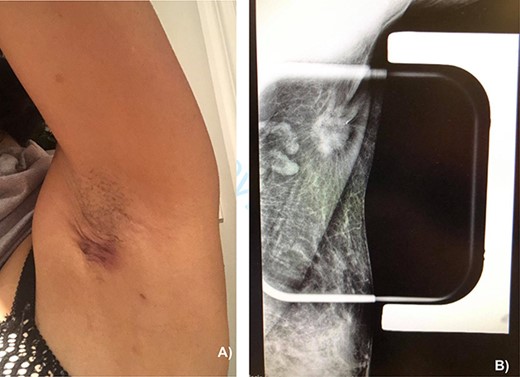

On physical exam, the patient had an area of erythema measuring 4 × 3 cm in the left axilla, with palpable skin thickening and subcutaneous edema (Fig. 1A). An initial mammogram showed an irregular axillary lesion extending to the skin, arising in ectopic breast tissue (Fig. 1A). A subsequent ultrasound showed skin thickening and a spiculated mass measuring 8 mm within the axilla, without any abnormal axillary lymph nodes or breast lesions. Biopsy of the mass demonstrated invasive ductal carcinoma, which was estrogen receptor (ER) positive, progesterone receptor (PR) positive and HER-2 positive. The sample also contained benign mammary gland elements, supporting a tumor localization in ectopic axillary mammary tissue. A magnetic resonance imaging (MRI) study showed no suspicious breast lesions or axillary lymph nodes, and confirmed the known axillary mass with skin extension (Fig. 2). Complete staging by whole-body positron emission tomography (PET) scan and brain computed tomography (CT) scan showed no evidence of metastatic disease.

(A) Appearance of the left axillary lesion at presentation. (B) Magnified view on mammogram of the left axilla showing an irregular mass with extension to the skin in the context of an ectopic mammary gland.